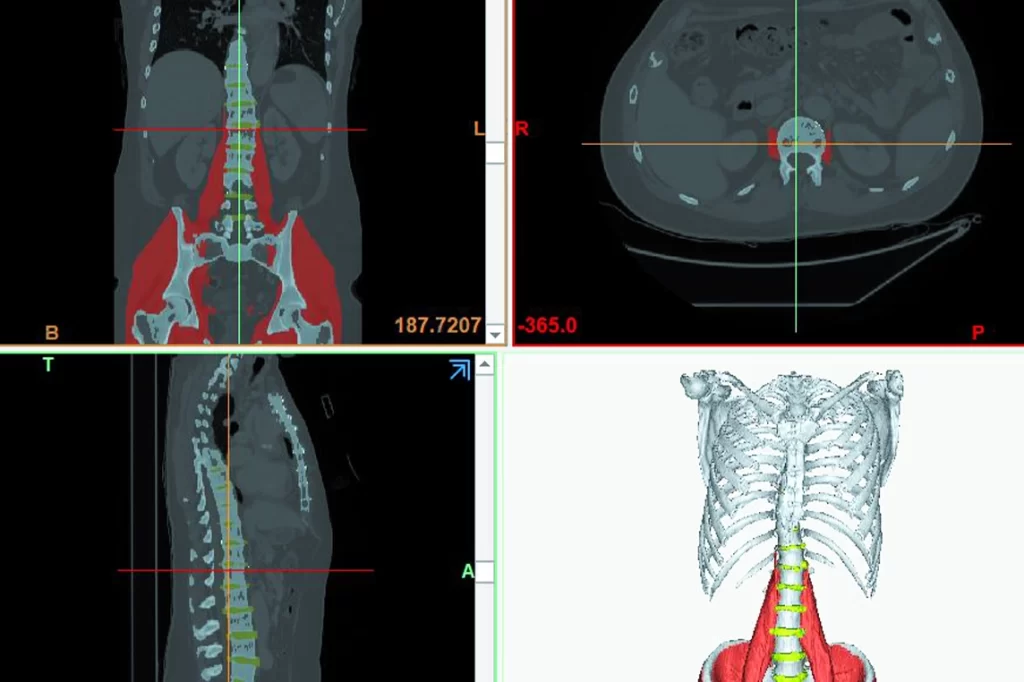

La segmentazione è l’elaborazione delle immagini mediche digitali, come TAC e RM. È un processo di partizione delle immagini in regioni significative che può essere eseguita manualmente, in maniera semiautomatica o automatica a seconda delle capacità ingegneristiche e dei software utilizzati. Permette di estrarre dalle immagini diagnostiche particolari anatomici, semplificandone la visualizzazione e la rappresentazione.

Siamo dotati di un software di segmentazione di alto livello che insieme alle nostre capacità ingegneristiche altamente specializzate permette di soddisfare le vostre richieste, come modelli pazienti-specifici per il singolo caso clinico e soluzioni customizzate.

Siamo in grado di fornirvi servizi di visualizzazione e condivisione dei modelli 3D digitali segmentati, per supportare i medici nella pianificazione chirurgica preoperatoria o nella condivisione con altri medici o nella comunicazione con i pazienti.